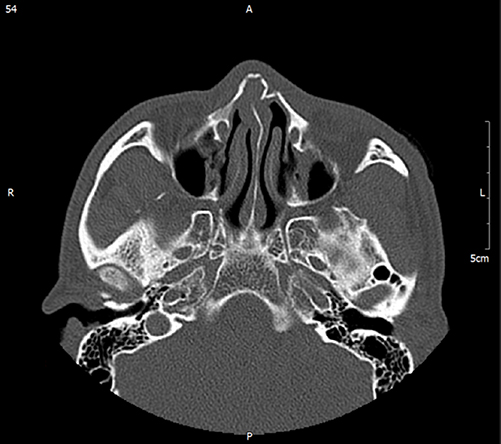

정확한 분석을 위한

체계적 진단골절의 원인을 CT를 통해

정확하고 입체적으로 분석 후

세밀한 상담으로 원인 분석 -